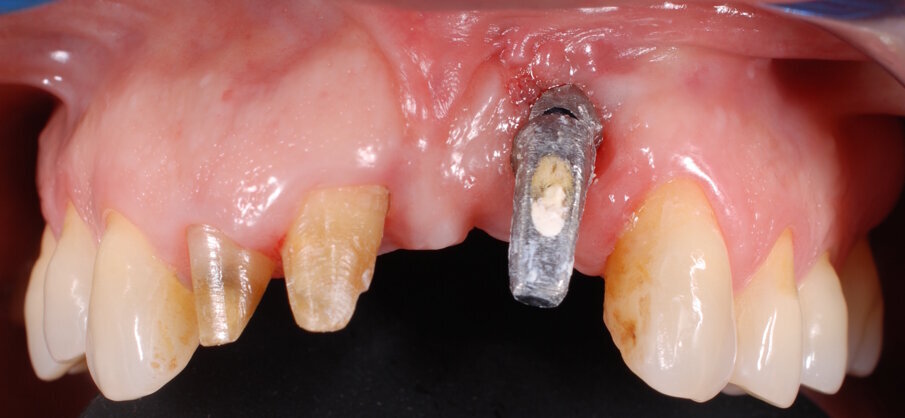

In questo articolo presentiamo un caso clinico che dimostra come il posizionamento improprio di un impianto può rendere impossibile la riabilitazione protesica, che richiede una nuova pianificazione chirurgica e riabilitativa per ottenere l’estetica desiderata. La paziente si presenta alla nostra osservazione con una riabilitazione protesica incongrua, con flangia in resina, a supporto dentale ed implantare, con la presenza di un impianto in posizione 2.1 vestibolarizzato e con l’emergenza nel fornice, in mucosa alveolare. Dalla valutazione della Tac si evince la posizione errata dell’impianto e la perdita consistente in senso trasversale della compagine ossea (Figg. 1, 2). Pertanto si opta per il seguente piano di trattamento che prevede: rimozione dell’impianto e preparazione protesica dell’elemento 2.3, confezionamento di un primo provvisorio a supporto dentale che servirà a guidare la guarigione dei tessuti (Figg. 3-7). A distanza di 4 mesi si procede a un innesto epitelio connettivale libero con prelievo dal palato per compensare il gap dei tessuti molli in senso trasversale, quindi viene ribasato il provvisorio in modo tale da favorire la guarigione dei tessuti (Figg. 8-11). A 9 mesi dalla maturazione dei tessuti si procede alla finalizzazione protesica fissa a supporto dentale (Figg. 12-14).

Fig. 1 - Situazione clinica iniziale.

Fig. 3 - Rimozione del manufatto protesico che evidenzia la posizione errata dell’impianto in sede 2.1.